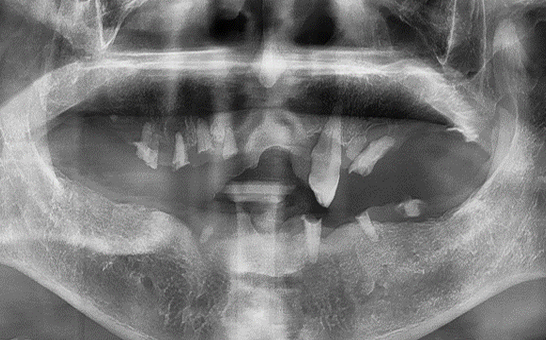

CASE 04 이** / 70대

전악임플란트

치료 시작 전 촬영 2022.06.05 | 치료 완료 후 촬영 2023.05.25

1 예후불량 치아 발치

2 발치 후 즉시 임플란트 식립 및 뼈이식

3 고정성 보철물로 수복 후 일상 회복